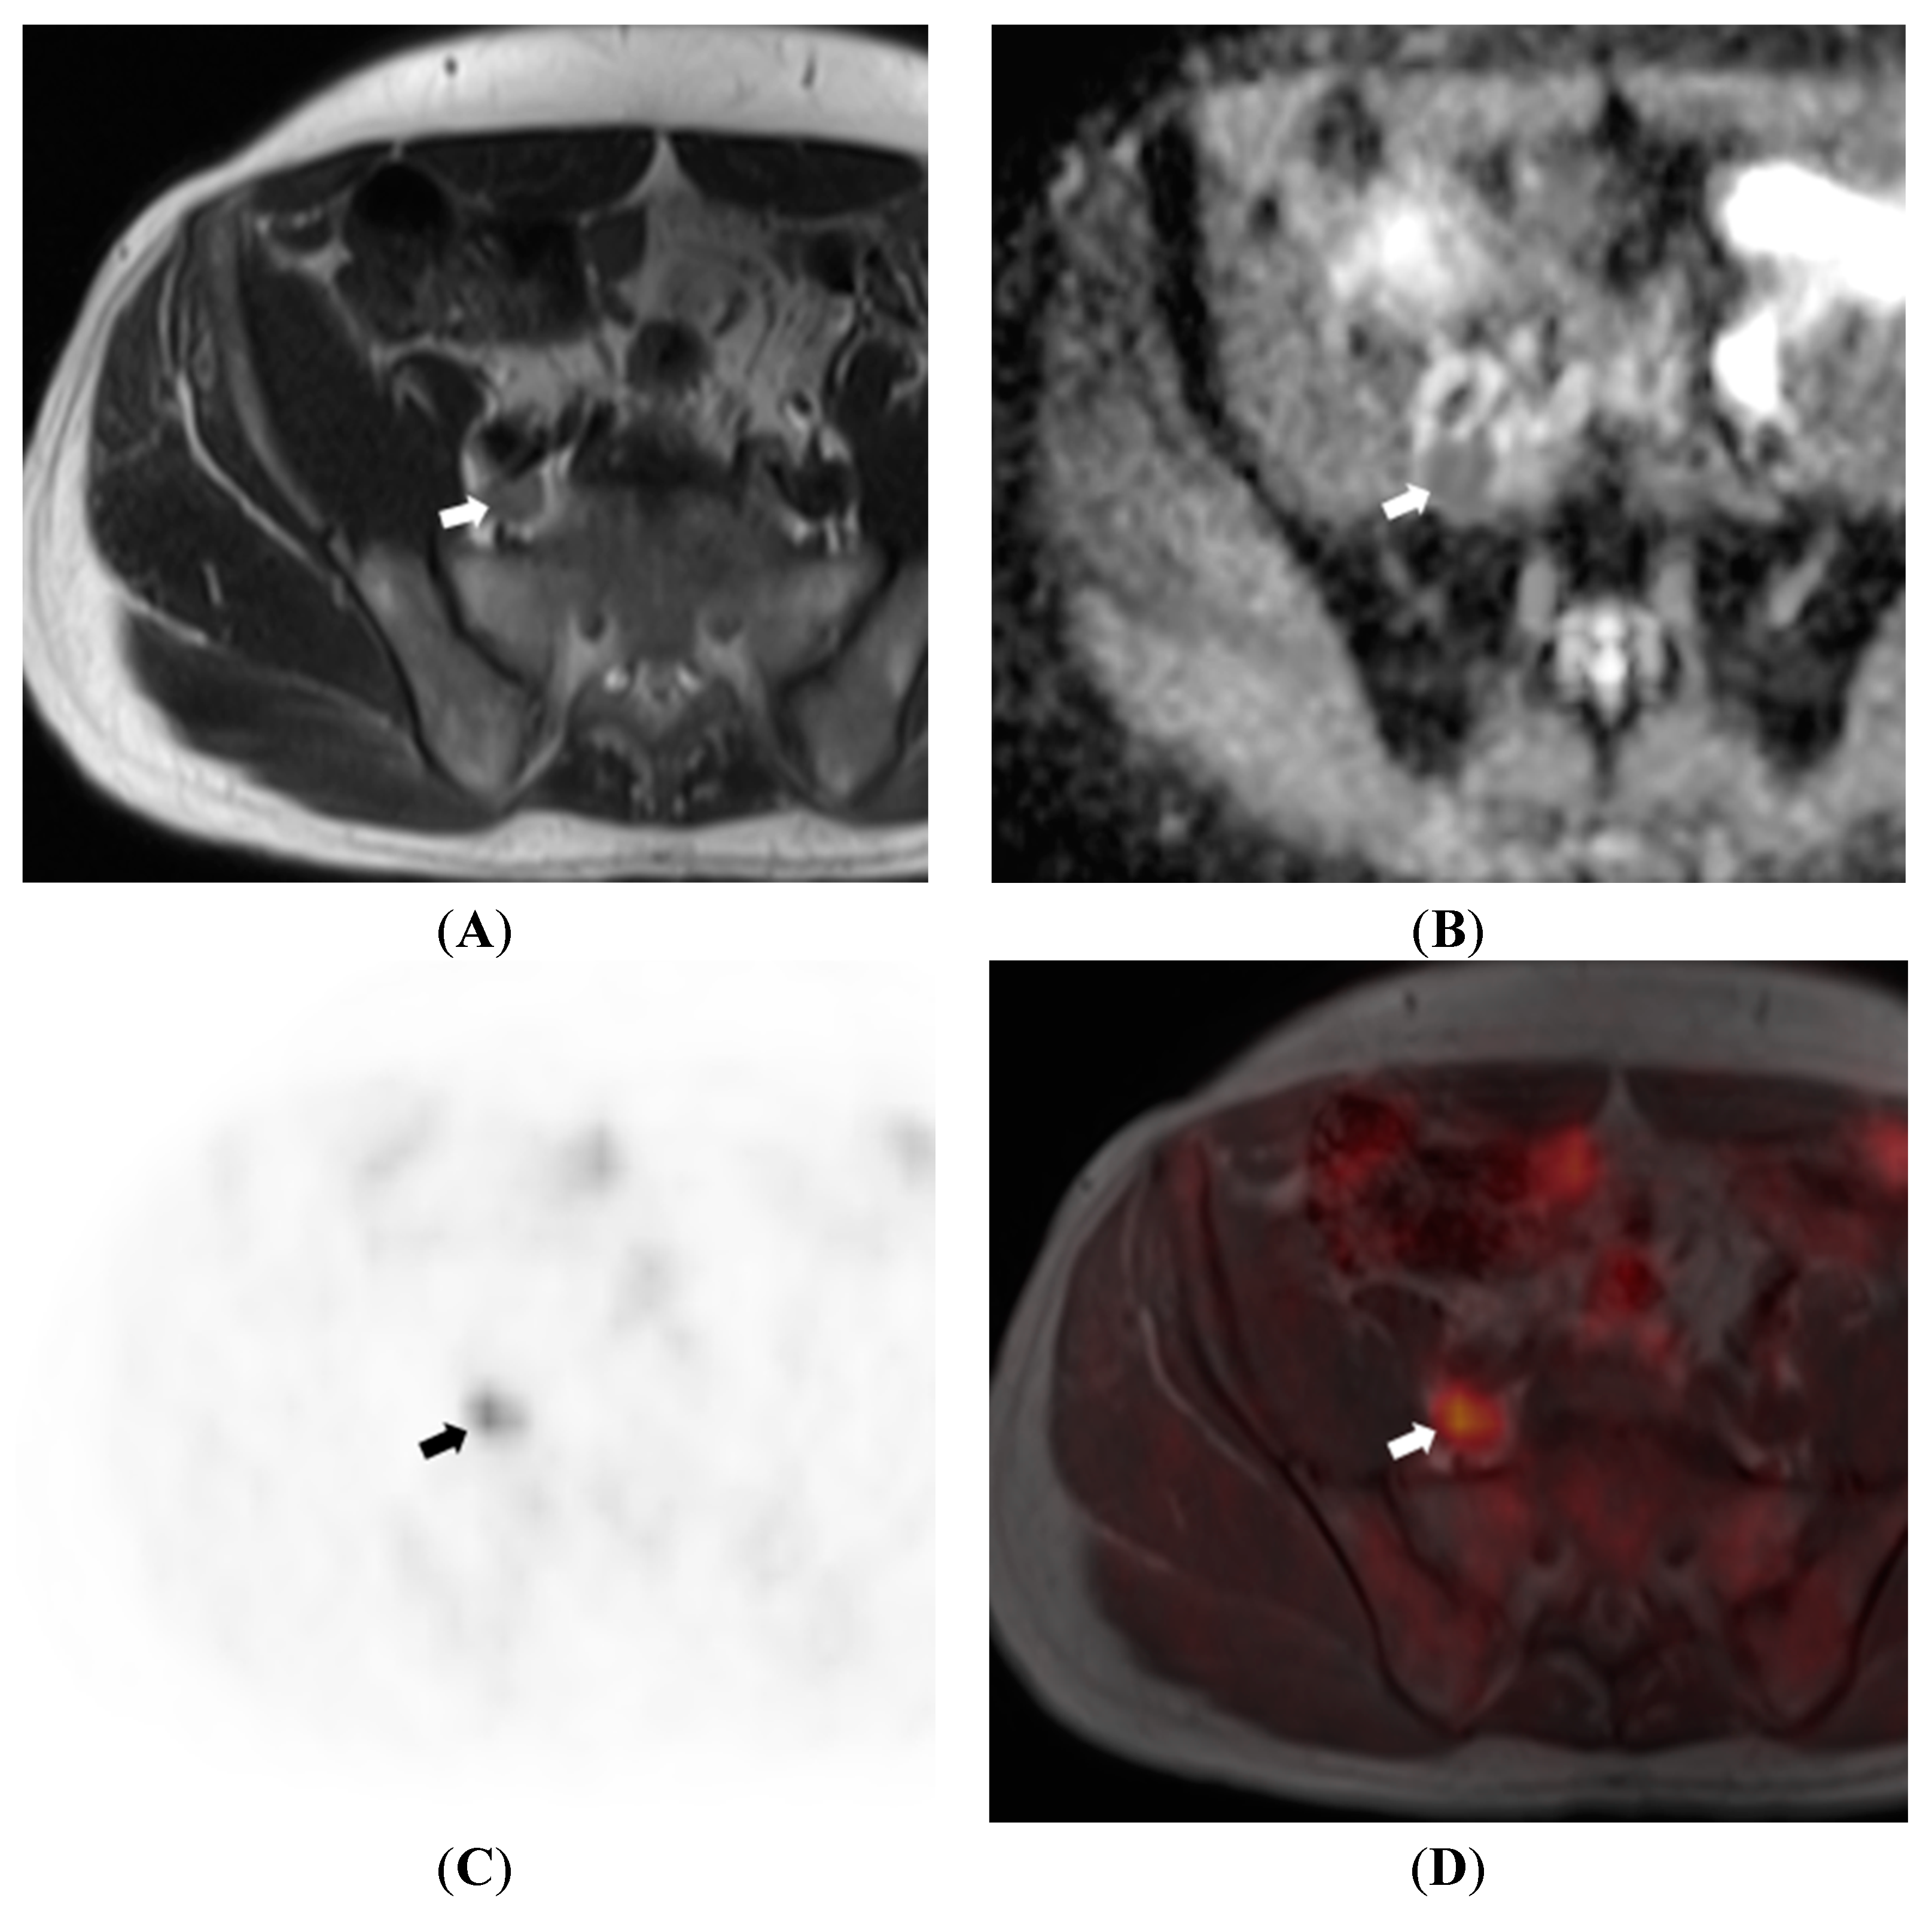

6. Nodal Assessment

- Kim, S.-K.; Choi, H.J.; Park, S.-Y.; Lee, H.-Y.; Seo, S.-S.; Yoo, C.W.; Jung, D.C.; Kang, S.; Cho, K.-S. Additional value of MR/PET fusion compared with PET/CT in the detection of lymph node metastases in cervical cancer patients. Eur. J. Cancer 2009, 45, 2103–2109. [Google Scholar] [CrossRef] [PubMed]